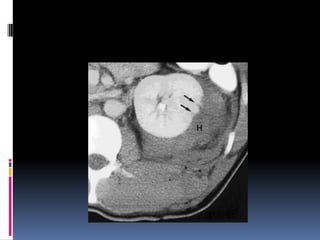

INJURIA RENAL - Clasificación I Contusion Microscopic or gross hematuria Hematoma Subcapsular, nonexpanding without parenchymal laceration

II Hematoma Nonexpandingperirenal hematoma confined to renal retroperitoneum Laceracion <1 cm parenchymal depth of renal cortex without urinary extravasation

III Laceration <1cm parenchymal depth of renal cortex without collecting system rupture or urinary extravasation

IV Laceration Parenchymallaceration extending through the renal cortex, medulla, and collecting system Vascular main renal artery or vein injury with contained hemorrhage

V Laceration Completelyshattered kidney Vascular Avulsion of renal hilum which devascularizes kidney